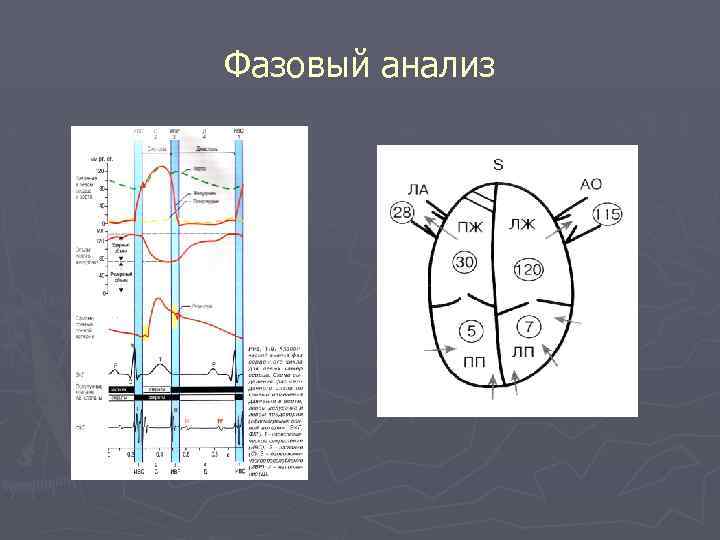

Фазовый анализ